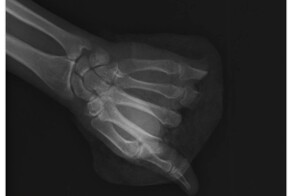

31-летний мужчина получил травму во время монтажно-строительных работ. У него была отсечена не только часть кисти в районе пястных костей, но и потеряна часть большого пальца.

Операцию проводили в Центре хирургии кисти и реконструктивной микрохирургии больницы им. С.С. Юдина. Врачи сшили под микроскопом все сухожилия, сосуды и нервы. Поврежденные кости восстановили с помощью остеосинтеза - фиксации фрагментов костей с помощью титановых пластин или штифтов.

Хирургическое вмешательство длилось 12 часов, и в результате врачам удалось восстановить кровоток и чувствительность отсеченной части кисти.